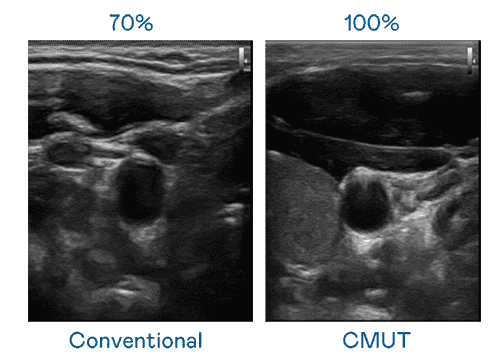

CMUT 技术是一种用电容式微机电元件来产生超音波讯号的技术。。。。与传统 PZT 压电式技术相比,,,CMUT 频宽增加 30%,,更宽频的超音波讯号让影像解析度大幅提升,,是实现高影像品质医疗超音波扫描、、、促进精准医疗发展的关键技术。。。。

大频宽带来超清晰影像

超音波影像的解析度高低,,,,首先取决于探头能发出的讯号频宽。。尊时凯龙 CMUT 可提供高清晰的超音波讯号,,提供高频宽、、、高灵敏度、、影像纹理细节更高的超音波影像,,协助医护人员缩短影像判读时间及利用精准的医疗影像进行诊断。。。。